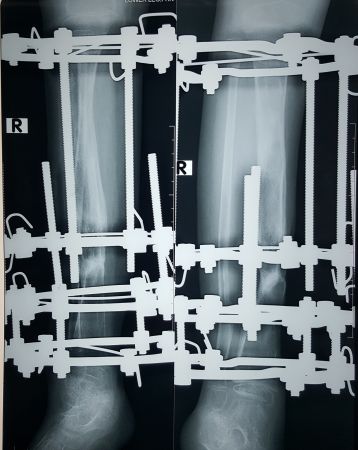

ইলিজারভ চিকিৎসা কি?

ইলিজারভ ১৯৫১ সালে রাশিয়ায়আবিষ্কৃত অর্থোপেডিক্স শাস্ত্রের একটি চিকিৎসা পদ্ধতি।

ইলিজারভ রিং/ ফ্রেইমটা কি?

এটি তৈরী হয় বিভিন্ন সাইজের ষ্টেইনলেস ষ্টিল/কার্বন এর রিং,রড-বোল্ট ও নাটের সংমিশ্রণে।তার দিয়ে যুক্ত থাকে শরীরের সাথে। আর ফ্রেইম গুলো নিখুতভাবে আকৃতি বিন্যাস করা হয় আলাদা আলাদা প্রয়োজন ও চাহিদা অনুযায়ী।

এই পদ্ধতিতে হাড়ধীরে ধীরে টানার ফলে রক্ত চলাচল বৃদ্ধি হয়ে নতুন হাড় তৈরি হয়। (Compression-distraction osteogenesis)

Law of tension stress: Theprocess of new bone and soft tissue regeneration under the effect oftension-stress caused by slow and gradual distraction

১) হাড় ভাঙ্গার চিকিৎসা (Treat fracture specially complex/open fracture)